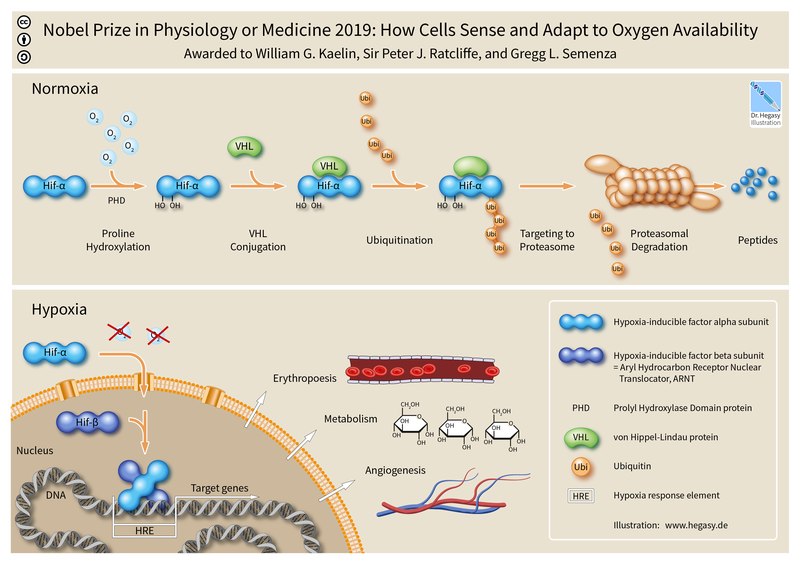

4 – Definitions: hypoxemia, hypercapnea, hypoxia, (an informative/summary figure can be made using Bio-render)

Hypoxia – is a condition involving abnormally low levels of oxygen in body tissues. It can lead to bluish skin, confusion, difficulty breathing, restlessness and fast heart rate. Hypoxia is different to hypoxemia as hypoxia is low oxygen levels in tissues whereas hypoxemia is low oxygen levels in blood.